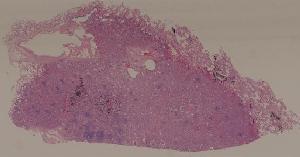

49. syphilitic aortitis

50. Labar pneumonia

51. Carnification of the lung

52. Lobular pneumonia

57. Carcinoma of the lung

59. Chronic atrophic gastritis

60. Gastric ulcer

61. Gastric adenocarcinoma(Mucinous adenocarcinoma of the stamoch)

62. Acute viral hepatitis (common type)

63.Chronic active viral hepatitis

64. Acute fulminant viral hepatitis

65. Subacute fulminant viral hepatitis

66. Active nodular cirrhosis of the liver

67. Inactive nodular cirrhosis of the liver

68. Biliary fibrosis

69. Hepatocellular carcinoma

72. Membranous glomerulonephritis

73. Acute glomerulonephritis

74. Crescentic glomerulonephritis

75. Chronic glomerulonephritis